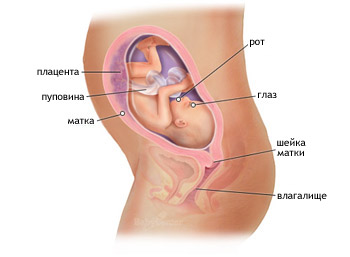

Зараз матка знаходиться над пупком майже на 7 см, а від лобкового симфізу вже відстоїть приблизно на 27 см. У цей період ви можете почати сильно набирати вагу.